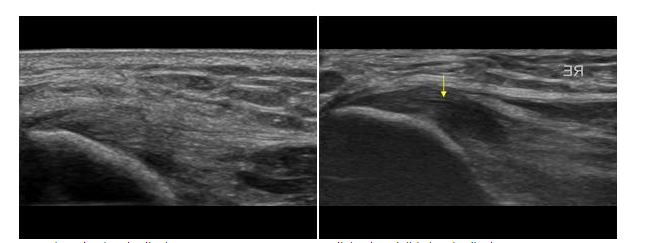

좌:정상, 우:비정상 @http://ultrasoundcases.info

근골격계 초음파로

양측 팔꿈치 내측을 스캔한 사진입니다.

정상인 좌측 사진에 비하여

우측의 힘줄이 까맣게 부어있고,

힘줄의 파열이 보입니다.

(노란색 화살표)